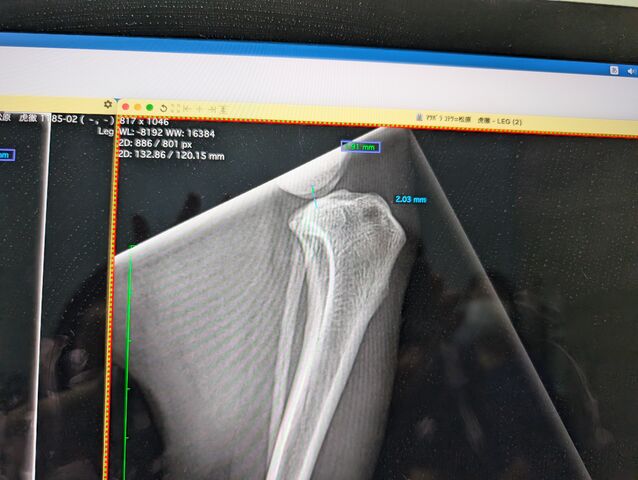

¤Á¤Ê¤ß¤Ë¤³¤Ã¤Á¤¬±¦É¨¤Î¥ì¥ó¥È¥²¥ó

¤³¤Ã¤Á¤¬ÃÇÎö¤·¤¿º¸É¨

´°Á´¤Ë¥º¥ì¤Æ¤Þ¤¹¡£